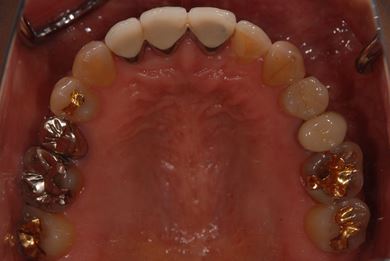

治療後

• 治療後